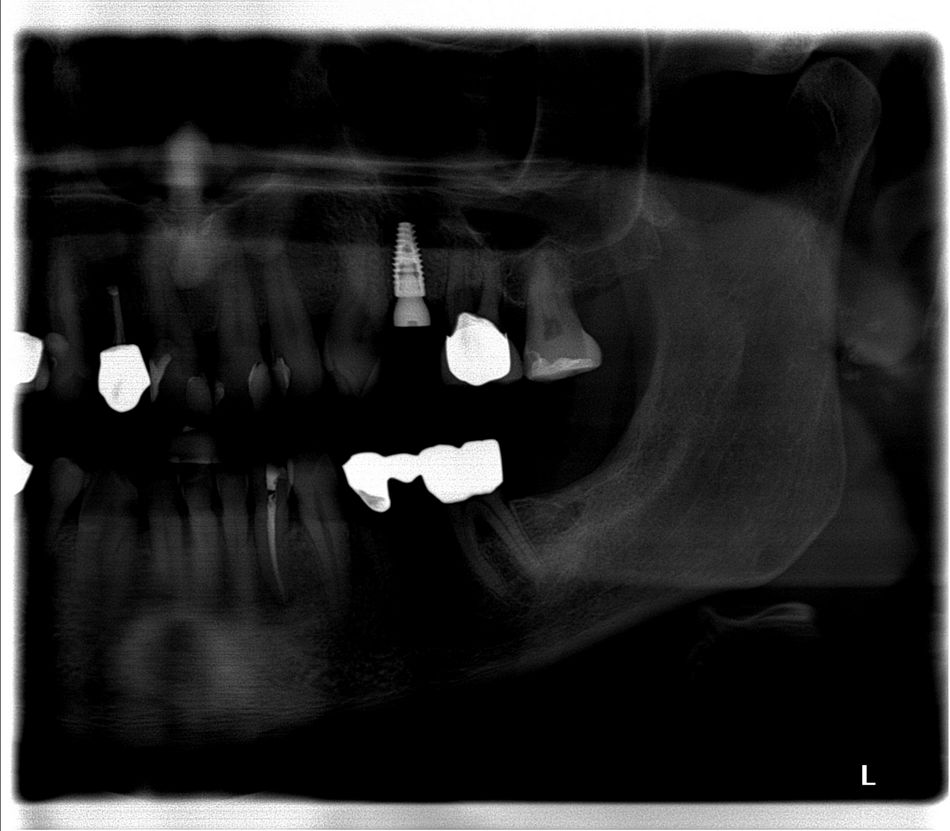

Der Patient stellte sich mit dem Wunsch der Versorgung der Schaltlücke regio 24 (Abb. 1) in unserer oralchirugischen Praxis vor. Die parodontale Vorbehandlung wurde bereits durch den Hauszahnarzt durchgeführt. Jedoch war die Prognose des furkationsbefallenen Zahnes 26 trotz mittlerweile unauffälligen Sondierungstiefen als prothetischer Pfeiler zu fraglich, um die Lücke mit einer konventionellen Brückenversorgung zu schließen.

Nach eingehender klinischer und radiologischer 3D-Diagnostik (Abb. 2, 3) wurde der Patient über eine notwendige laterale Augmentation mit xenogenem Ersatzmaterial und Eigenknochen aufgeklärt und die operationsbedingten Risiken wurden mit ihm besprochen.